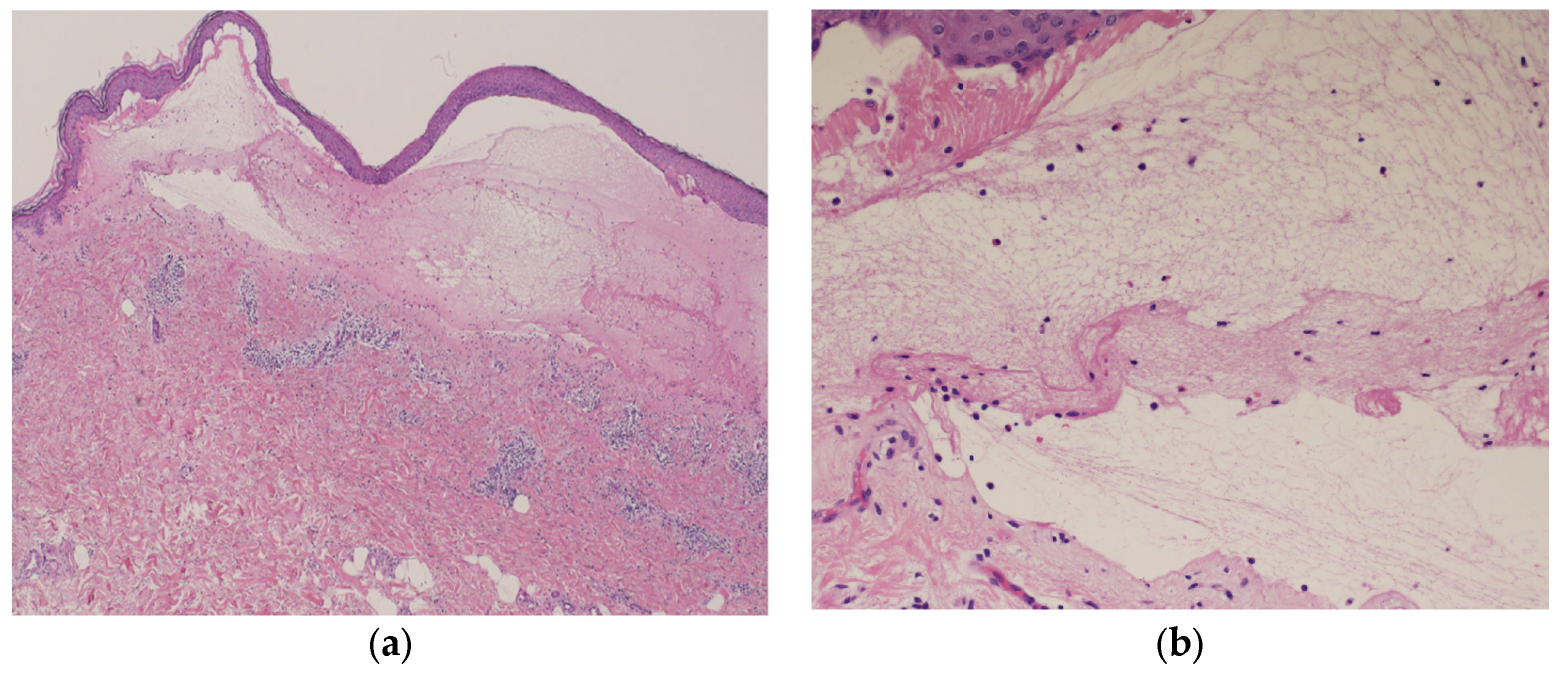

Blood tests showed normal eosinophil levels (417/μL) but elevated immunoglobulin (Ig) E levels (516 IU/mL). Antibody tests for bullous diseases were negative for anti-desmoglein 1 and 3 antibodies but positive for anti-BP180 antibodies (216). Histopathological examination of a biopsy specimen from the blistered area revealed subepidermal blisters with eosinophils and lymphocytes infiltrating the small blisters along with marked infiltration of inflammatory cells into the upper dermis (Figure 5a,b).

Figure 5.

Histopathological examination of the blistered area reveals subepidermal blisters (hematoxylin and eosin [HE] staining; ×40) (a); eosinophils and lymphocytes were infiltrating around the small blisters, along with marked infiltration of inflammatory cells in the upper dermis (HE staining; ×200) (b).